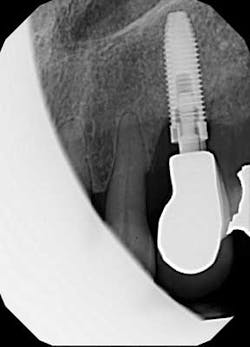

We seat the crown and take a periapical radiograph and find something odd.

Fig. 3: Periapical radiograph.

Looks like the original restorative dentist never fully seated the abutment! Perhaps that would explain why the patient believed the crown “never felt right.” We remove the abutment and see that there are no restorative margins to speak of, just a standard, prefabricated abutment that was used right out of the package. Since there is no sign of radiographic bone loss, the gingival erythema is diagnosed as peri-implant mucositis.